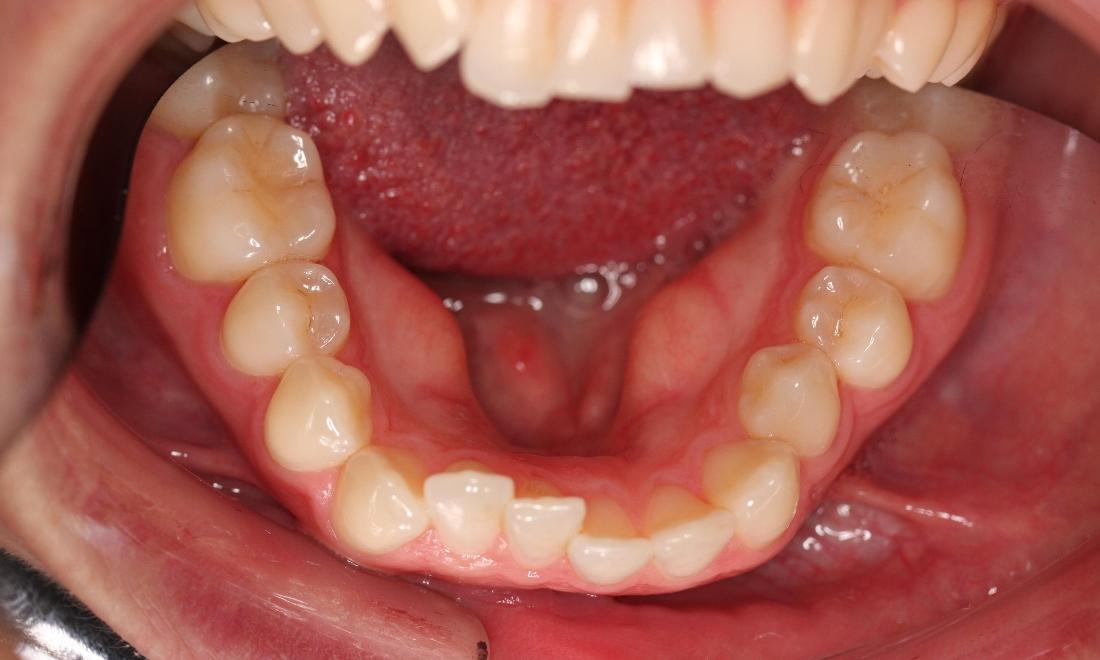

This young woman was self conscious about the crowding in her upper and lower teeth. After months of invisalign treatment, she is very satisfied with the result.